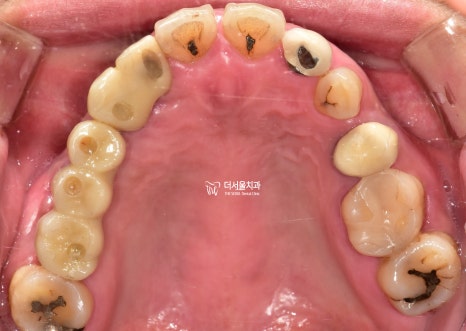

이분은 # 12 – # 15가

브릿지로 연결되어 있었는데요.

짐작하건대 매복치아 때문에

이렇게 길~~~~~~~게

연결을 해둔 것 같습니다.

그래서 그런지 수명이 짧을 수밖에요.